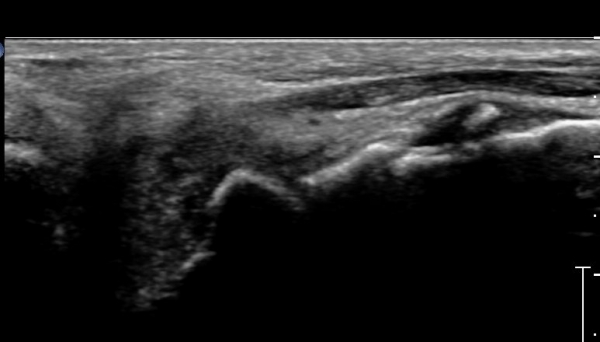

Á¾°ñÀÔ¹æ°ñ°üÀý Á¾´Ü¸é°Ë»ç»ó Á¾°ñ Àü¹æµ¹±â °ß¿­°ñÀý°ú Á¦4ÁßÁ·°ñ °ß¿­°ñÀýÀÌ °üÂûµÈ´Ù(»çÁø 2).